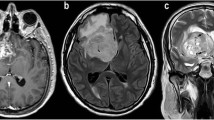

Example of ROI placement in a posterior fossa medulloblastoma. The ROI positioned on the CBV map over the solid part of the tumor and the control ROI in left cerebellar grey matter are automatically overlaid on the other perfusion (corrected CBV, K2, MTT, TTP, tMIP) and ADC maps, as well as on T2WI and post-GBCAs T1WI. This prevents the inclusion of macroscopic vessels within the ROI. The perfusion curve is at the top left. Supplementary material 1 (TIFF 5605 kb)